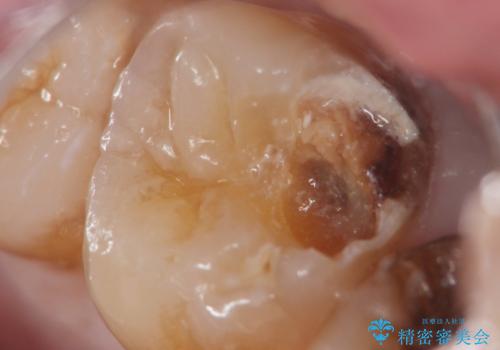

精査したところ、神経近くに及ぶ大きなう蝕を認めました。

神経をとらずに済むよう丁寧にう蝕を除去したのち、セラミックインレーで修復しました。

詰め物の種類:セラミックインレー (e-max press)